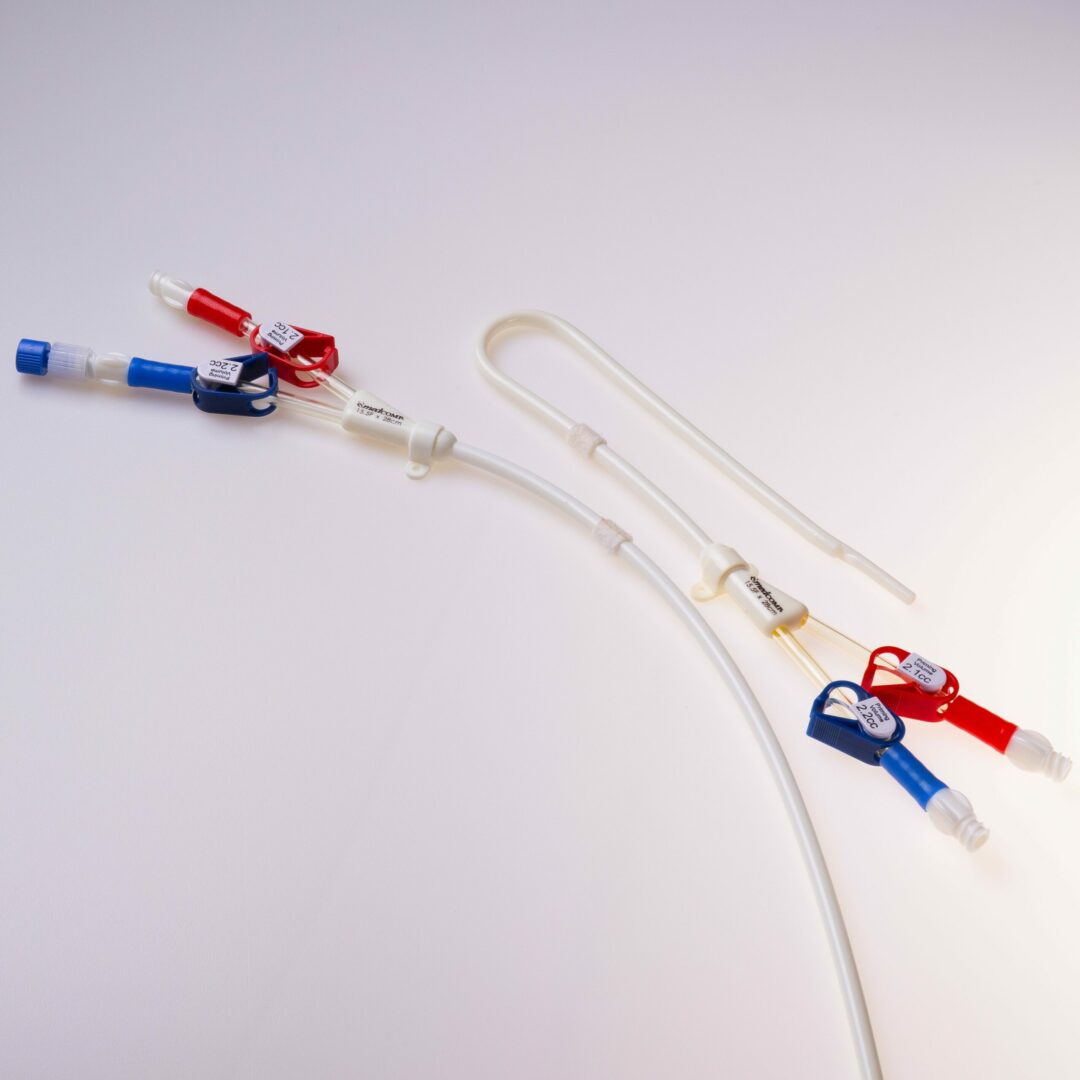

Der THD Titan® ist ein untertunnelter Langzeitdialysekatheter für die chronische Hämodialyse. Er ermöglicht einen mehrjährigen, verlässlichen Gefäßzugang im Dialysebetrieb mit sehr hohen durchschnittlichen Flussraten aufgrund großer Lumina von 15,5 French: die erzielbaren Katheter – Flussraten liegen jenseits von 450 ml / Min.

Der THD Titan® ist ein untertunnelter Vorhofkatheter für die chronische Hämodialyse.

Der THD Titan® wird antegrad untertunnelt. Die Einführung in das Gefäß erfolgt entweder über eine Splitkanüle mit Schleuse oder über einen Führungsdraht in der OTW – Technik ( over the wire ). Ein Innenmandrin zur Unterstützung der OTW – Technik ist standardmäßig in jedem Katheter enthalten.

Set Komponenten der E (gerade) und PCE (precurved) Version